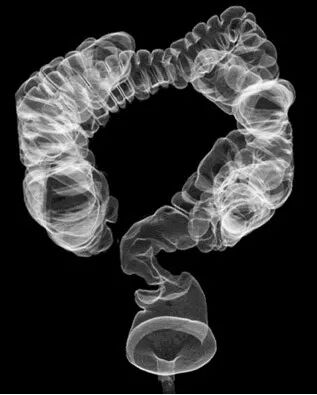

胃肠机是一种用来检查胃肠道疾病的X线检查设备,它可以通过注入碘油等造影剂,让胃肠道的形态和功能在屏幕上清晰可见,从而帮助医生诊断各种溃疡、肿瘤、异物等疾病。胃肠机不仅可以进行静态的拍摄,还可以进行动态的观察,实时地跟踪胃肠道的蠕动、排空、反流等情况。胃肠机还可以配合内镜等器械,进行一些微创的治疗操作,如食道或结肠的支架置入、胆管或胰管的造影和引流等。